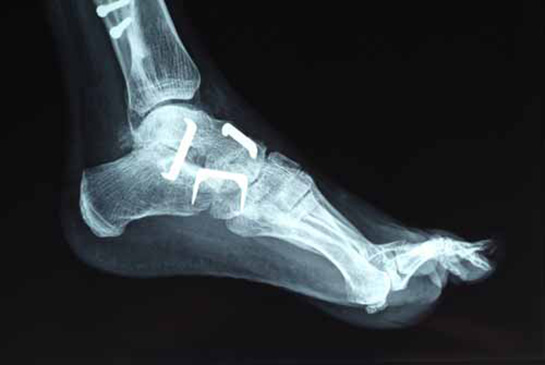

• Cerrahi Müdahale: Eğer çatlak ciddi bir seviyedeyse ve kemiklerin hizalanmasında sorun varsa, cerrahi müdahale gerekebilir. Bu durumda, cerrah tarafından çatlağın onarılması işlemi gerçekleştirilir.